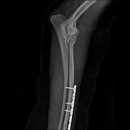

• 24시 에피소드 동물 메디컬 센터 | 만촌동 동물병원 강아지 요골·척골 골절 수술 후기 [24시에피소드동물메디컬센터]

만촌동 동물병원 강아지 요골·척골 골절 수술 후기 [24시에피소드동물메디컬센터] 만촌동 동물병원 ​ 안녕하세요. ​ 풍부한 경험과 따듯한 진료를 바탕으로, 반려동물의 건강하고 행복한 하루하루를 함께 만들어 가는 만촌동 동물병원 24시에피소드동물메디컬센터 입니다. 24시에피소드동물메디컬센터 대구광역시 동구...

에피소드동물메디컬센터(2025-06-26 12:41:00)